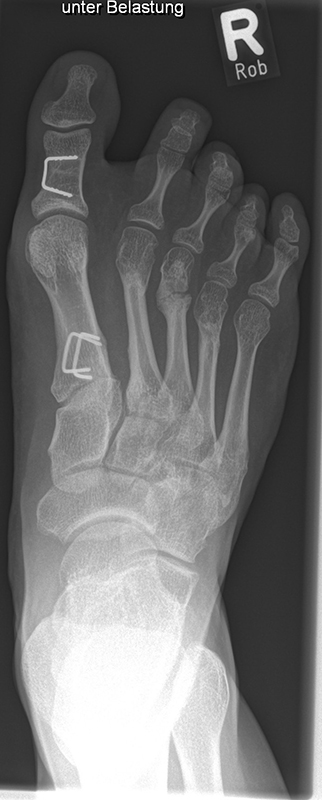

Abb. 2 a-c: offene Wachstumsfugen MT I Basis und Zehen (a), teilweise geöffnete Wachstumsfugen (b) und geschlossene Wachstumsfugen (c).

Zum Lesen der Bildbeschreibung und zur Vollansicht bitte die Bilder anklicken. Bilder: A. Helmers.